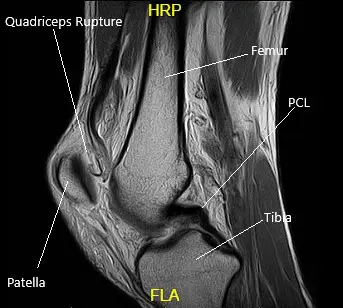

MRI suggested a complete rupture of the quadriceps tendon at the patellar attachment. The joint effusion communicates through the tendon defect with a prepatellar fluid collection. Low-grade intrasubstance tear at the origin of the ACL. Radial tear at the free edge of the lateral meniscal body.

MRI of the Left Knee in the sagittal section.